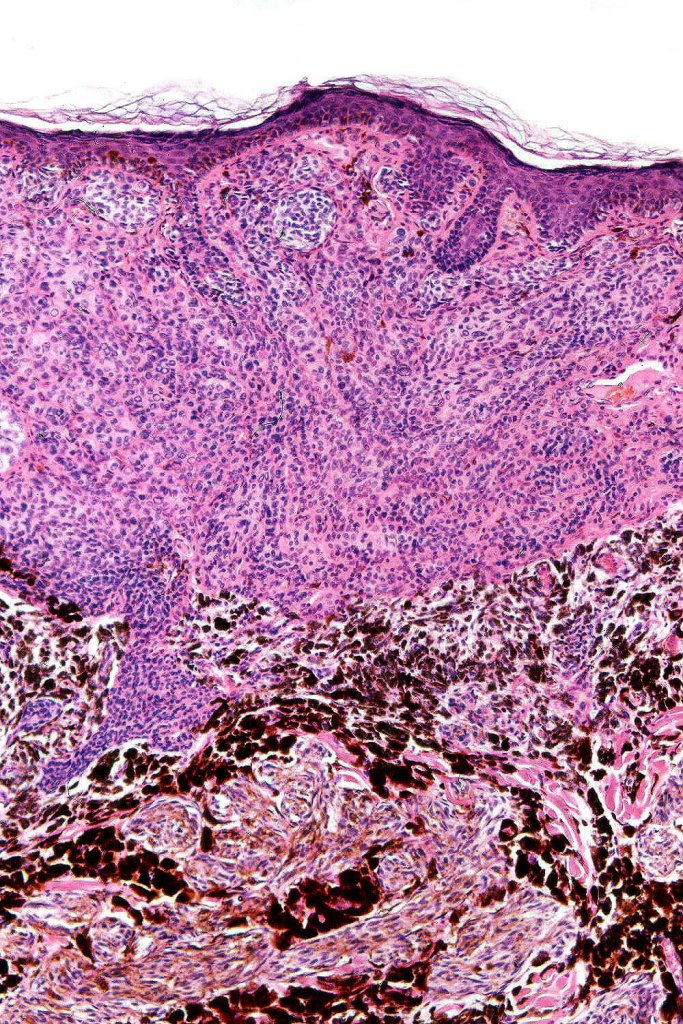

Combined congenital & blue nevus (same case as the clinical photographs coursty of Dr. Antonina Kalmykova